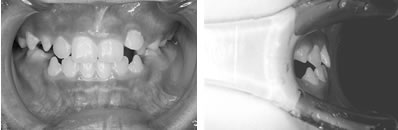

パノラマレントゲンで前歯部分に過剰歯などの異常が無いことを確認。セファログラムレントゲンの分析から、左上の1番目の永久歯(中切歯)が内側に入っていることが問題であることを確認。

その後、木ヘラ(アイスの棒など)を用いて、歯を外側に出すトレーニングを行いました。